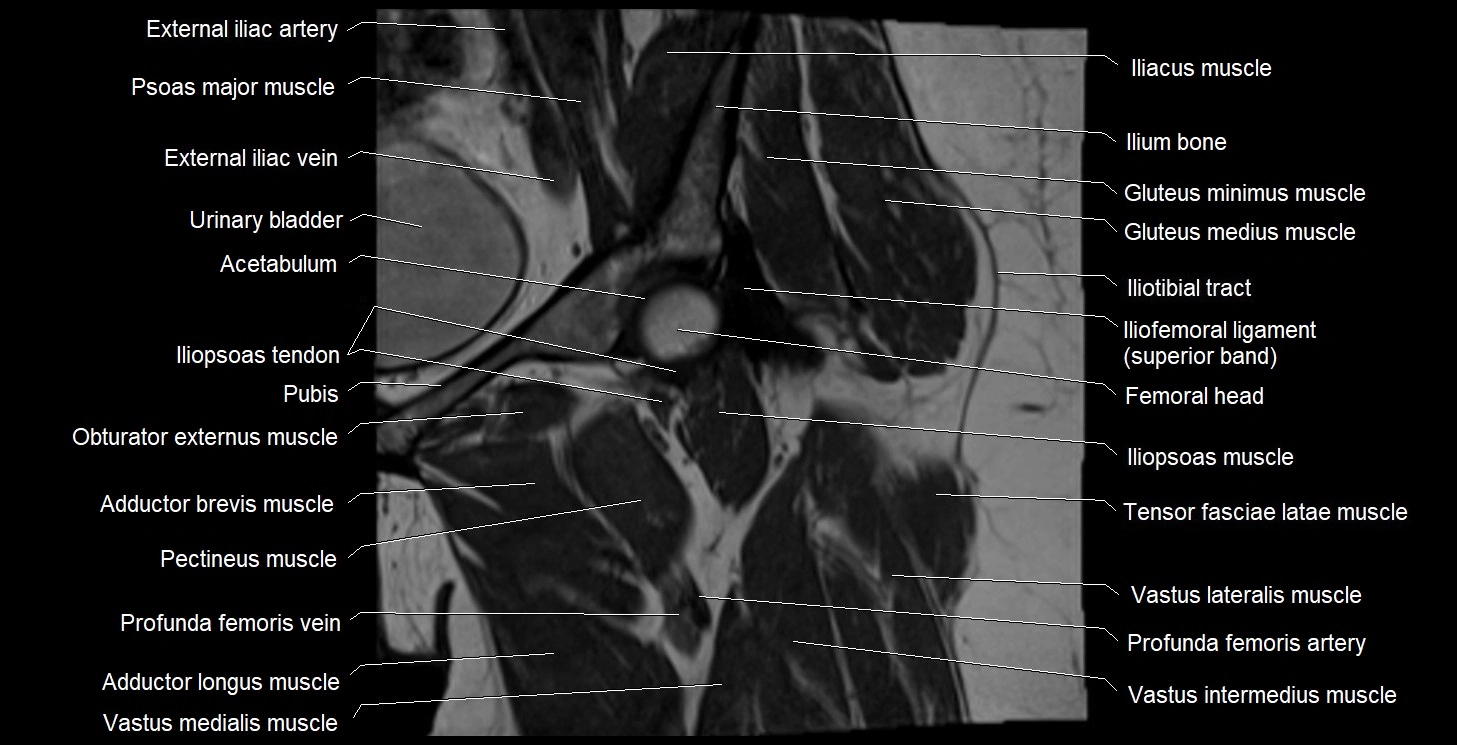

- Acetabulum

- External iliac artery

- External iliac vein

- Gluteus medius muscle

- Gluteus minimus muscle

- Iliofemoral Ligament superior band (transverse band, lateral band)

- Iliopsoas muscle

- Iliopsoas tendon

- Iliotibial tract

- Ilium bone

- Obturator externus muscle

- Pectineus muscle

- Rectus femoris muscle

- Tensor fasciae latae muscle

- Vastus intermedius muscle

- Vastus lateralis muscle

- Vastus medialis muscle